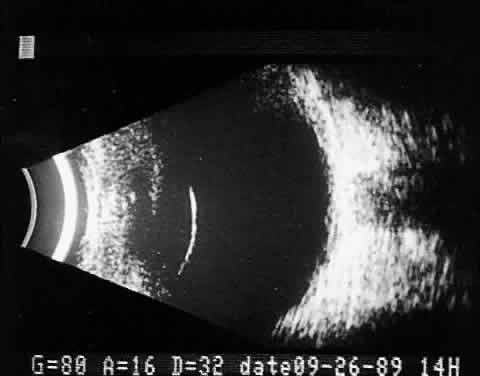

Fig. 4. Immersion B-scan. B. Simultaneous A-scan, vertical format. Cornea and anterior segment are seen easily with waterbath stand-off. A-scan is imaged separately to the side. (Courtesy of DJ Coleman, MD, and Sue Woods, ultrasound laboratory, New York Hospital.)